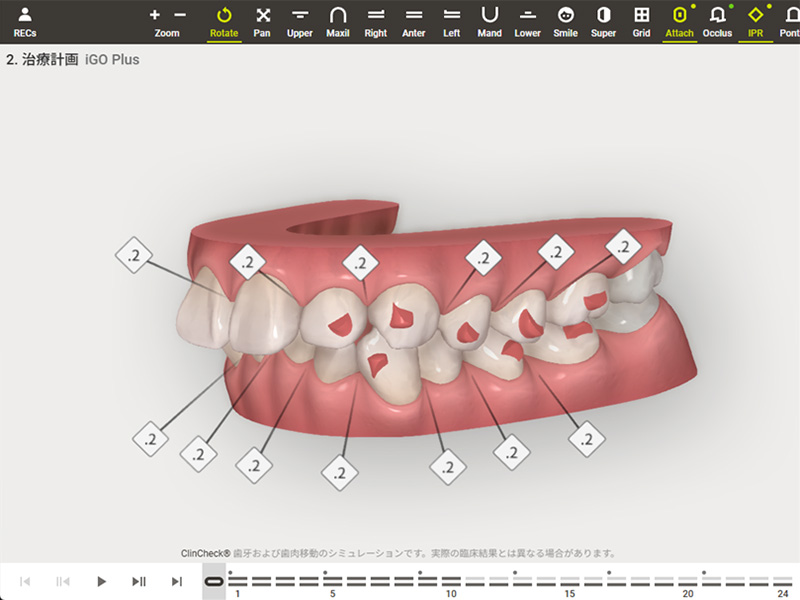

| デジタル診断 | 光学スキャナーで歯型を採取し、3Dシミュレーションで治療計画を立案。 |

クリンチェック(治療計画の説明)

一人ひとりに合わせた歯並びの変化を、3Dシミュレーションでご確認いただけます。